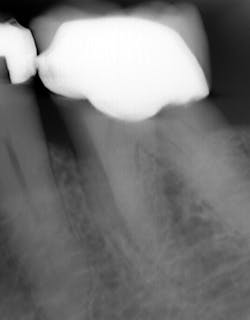

What’s unique about this system is that it uses nanotube technology to capture standard 2D images (figure 2) and gives you the option of taking a tomosynthesis image, which captures multiple images from several angles (figure 3). Images are compiled into a sliced volume and dissected into 0.5 mm or 0.1 mm slices that you can scroll through, rotate, enlarge, measure, and adjust. The system can “un-overlap” many teeth; this is convenient because with regular 2D x-rays, I had to retake the image at different angles and often with little success.